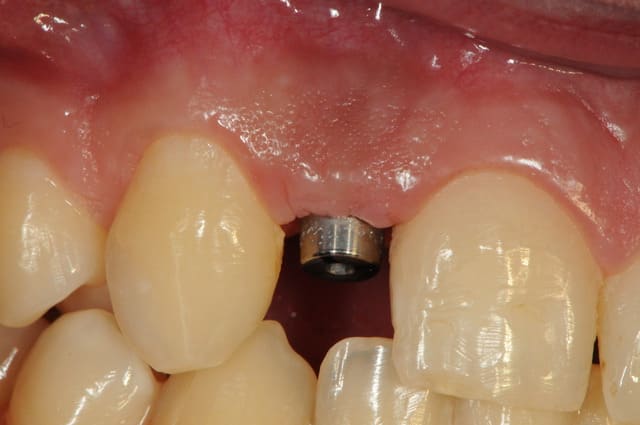

je reviens sur ce cas que j'ai un peu délaissé...

il est terminé, j'ai juste oublié de mettre la suite.

-cicatrisation

-mise en place vis de cica petit diamètre

-ensuite on augmente le diamètre en conservant et en gonflant les tissus gingivaux